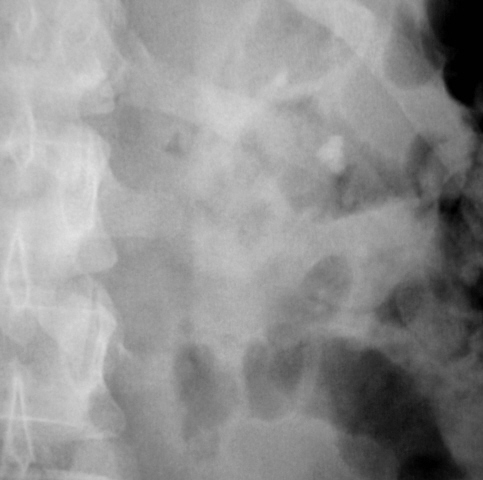

Иллюстрации 8, 9. Четко дифференцируются конкременты в малых чашечках левой почки. Справа определяется контрастирование малых чашечек в виде нечётко очерченных «лужиц».

Иллюстрации 6, 7. После введения контрастного вещества функция с обеих сторон. Слева почка обычного расположения, формы и размеров. Вышеописанные конкременты располагаются в эктазированных малых чашечках. Мочеточник обычного калибра, прослеживается на всем протяжении.